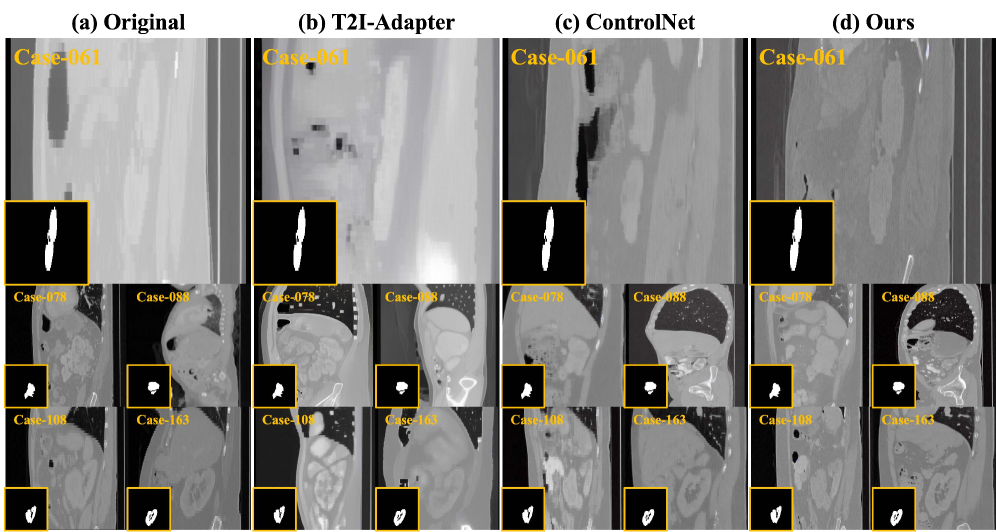

Refer to caption

Figure 3: Examples of real and synthetic kidney tumor images generated by each method.

Fig. 3 and Fig. 4 present kidney tumor and polyp images generated by various methods. SinGAN [29], although designed for the Polyps dataset, often introduces artifacts and lacks diversity. ArSDM [5] suffers from texture degradation in polyps and fails to generalize to KiTS19 due to its task-specific nature. T2I-Adapter [17] generates unrealistic textures in RGB data and underperforms on CT data. ControlNet [36] struggles with mask-lesion alignment. In contrast, our model excels in both mask-lesion alignment and morphological features, clearly outperforming the others.